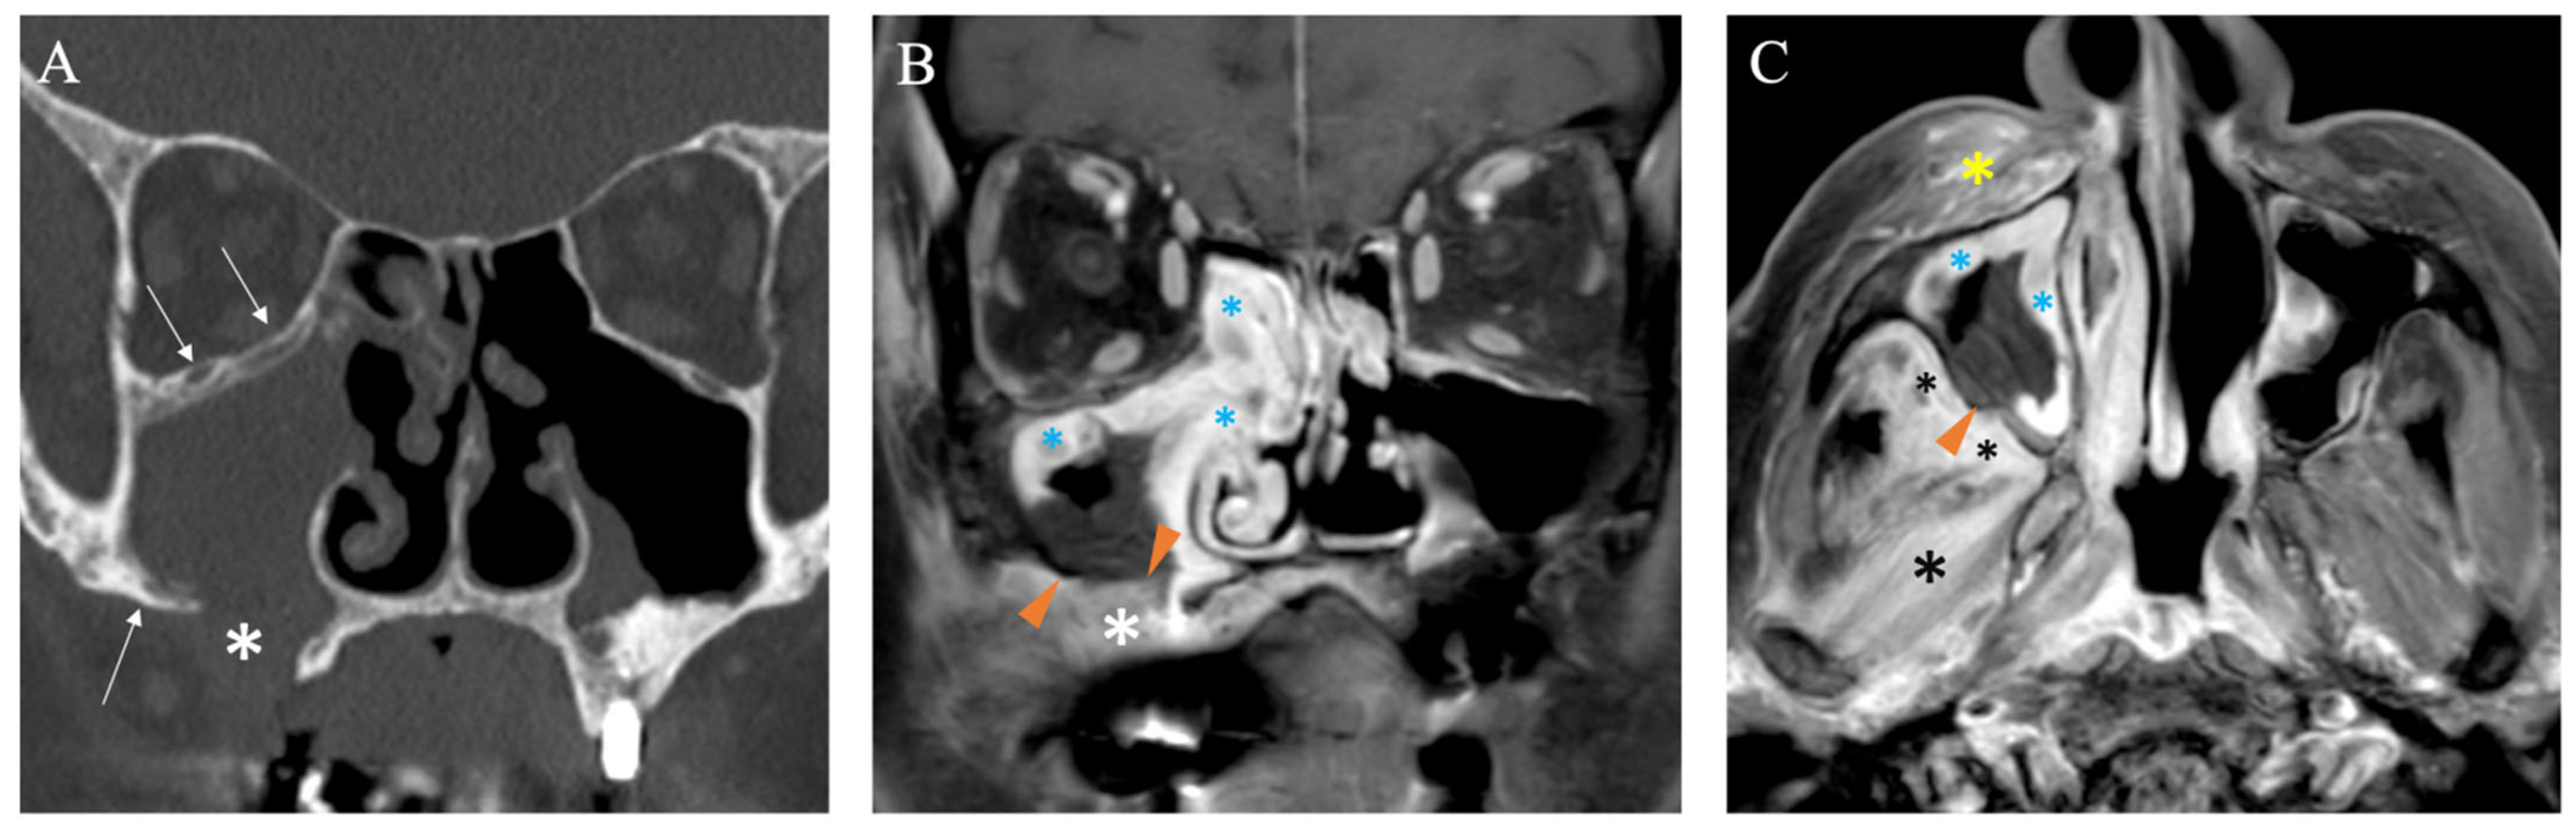

- Dixit, R.; Gupta, A.; Prakash, A.; Pradhan, G.S. Magnetic resonance imaging of rhino-orbito-cerebral mucormycosis: A pictorial review. Acta Radiol. 2023, 64, 1641–1649. [Google Scholar] [CrossRef]

- Safder, S.; Carpenter, J.S.; Roberts, T.D.; Bailey, N. The “Black Turbinate” sign: An early MR imaging finding of nasal mucormycosis. AJNR Am. J. Neuroradiol. 2010, 31, 771–774. [Google Scholar] [CrossRef]

- Han, Q.; Escott, E.J. The Black Turbinate Sign, A Potential Diagnostic Pitfall: Evaluation of the Normal Enhancement Patterns of the Nasal Turbinates. AJNR Am. J. Neuroradiol. 2019, 40, 855–861. [Google Scholar] [CrossRef]

- Tashi, S.; Purohit, B.S.; Becker, M.; Mundada, P. The pterygopalatine fossa: Imaging anatomy, communications, and pathology revisited. Insights Imaging 2016, 7, 589–599. [Google Scholar] [CrossRef]

- Becker, M.; Masterson, K.; Delavelle, J.; Viallon, M.; Vargas, M.I.; Becker, C.D. Imaging of the optic nerve. Eur. J. Radiol. 2010, 74, 299–313. [Google Scholar] [CrossRef]